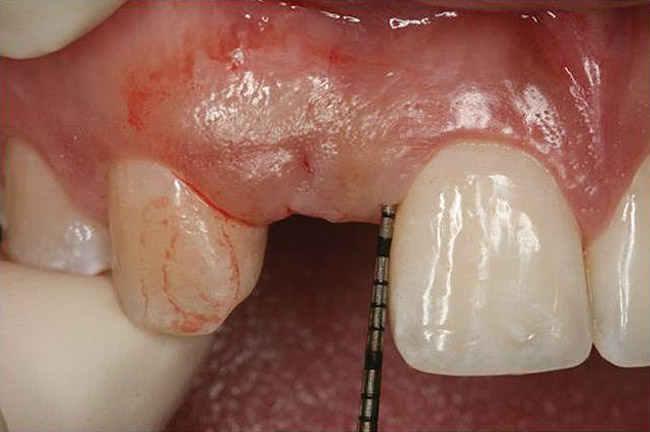

Figure 10  Clinical examination of the bound edentulous space: Measurement of the distal (Fig 10) and mesial (Fig 11) interproximal tissue height using a periodontal probe supplements data obtained from the periapical radiograph. Estimation of the buccal tissue thickness (bone sounding) is performed at the determined location of the gingival zenith using a guide developed from the diagnostic waxing (Fig 12).

Figure 10

Figure 11   Clinical examination of the bound edentulous space: Measurement of the distal (Fig 10) and mesial (Fig 11) interproximal tissue height using a periodontal probe supplements data obtained from the periapical radiograph. Estimation of the buccal tissue thickness (bone sounding) is performed at the determined location of the gingival zenith using a guide developed from the diagnostic waxing (Fig 12).

Figure 11

Figure 12   Clinical examination of the bound edentulous space: Measurement of the distal (Fig 10) and mesial (Fig 11) interproximal tissue height using a periodontal probe supplements data obtained from the periapical radiograph. Estimation of the buccal tissue thickness (bone sounding) is performed at the determined location of the gingival zenith using a guide developed from the diagnostic waxing (Fig 12).

Figure 12